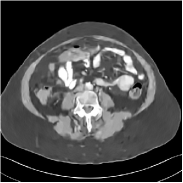

This special case of SUPER corresponds to the case where SUPER excludes the unsupervised regularizer, while only involves the data-fidelity and a supervised regularizer in the MBIR cost, i.e., β=0𝛽0\beta=0 and μ0𝜇0\mu\neq 0. In this case, the proposed SUPER model is similar to a generalized block coordinate descent-based network by replacing a simple denoising autoencoder [28, 29, 30] with a general CNN that forms our supervised regularizer. This SUPER is also similar to the plug-and-play ADMM-Net method except that the inputs to each supervised network are the preceding reconstructions, while plug-and-play ADMM-Net updates inputs to the network (denoiser) based on auxiliary variables in the ADMM algorithm. Here, we used μ=1×106𝜇1superscript106\mu=1\times 10^{6}, which worked well for the plug-and-play ADMM-Net method, for this special case of SUPER. Fig. 7 shows a comparison between plug-and-play ADMM-Net, SUPER without unsupervised regularizers (in both training and testing), and the full SUPER version with ULTRA regularization (β=5×103𝛽5superscript103\beta=5\times 10^{3}, μ=5×105𝜇5superscript105\mu=5\times 10^{5}). All these methods used WavResNet as their denoisers/supervised networks. In this example, SUPER with only a supervised regularizer (SUPER-WRN-β=0𝛽0\beta=0) outperforms the plug-and-play ADMM-Net (ADMM-Net (WRN)) by 1.6 HU RMSE and provides sharper image details. Comparing SUPER-WRN-β=0𝛽0\beta=0 and the full SUPER-WRN-ULTRA scheme, we observe that the latter provides a lower RMSE and higher contrast image features than the former that excludes the unsupervised component. This again shows the effect of the unsupervised ULTRA model (in capturing local image details better with a union of learned transforms) in the SUPER scheme.

Refer to captionADMM-Net (WRN)RMSE = 32.90 HURefer to captionADMM-Net (WRN)RMSE = 32.90 HU

Refer to captionSUPER-WRN-β=0𝛽0\beta=0RMSE = 31.32 HURefer to captionSUPER-WRN-β=0𝛽0\beta=0RMSE = 31.32 HU

Refer to caption SUPER-WRN-ULTRARMSE = 29.74 HURefer to caption SUPER-WRN-ULTRARMSE = 29.74 HU

Refer to caption ReferenceRefer to caption Reference

Figure 7: Reconstructed images of L192 slice 150 with WavResNet plugged ADMM-Net, SUPER-WRN-β=0𝛽0\beta=0 (both training and testing), and SUPER-WRN-ULTRA (β=5×103𝛽5superscript103\beta=5\times 10^{3} in both training and testing), respectively, shown with the reference image.